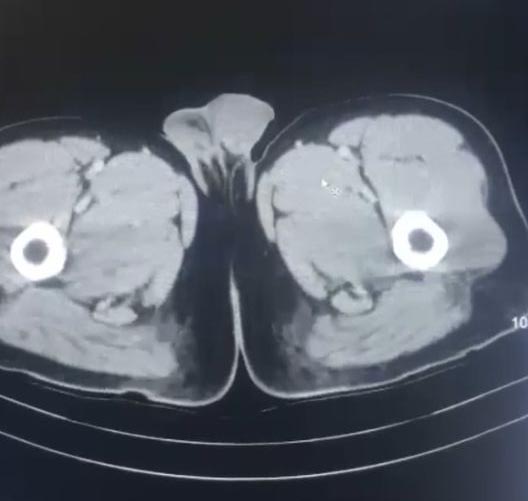

Şüpheliler düzenlenen operasyonla gözaltına alındı. 3 şüpheli muayene olmak üzere Kayseri Şehir Hastanesi'ne getirildi. Röntgen ve ultrason sonrası kontrollerde 3 şüphelinin midesinde uyuşturucu madde olduğu belirlendi.

Şüphelilerin yaklaşık 17 kapsül halinde 212,8 gram uyuşturucu yuttuğu tespit edildi. Kapsüller, sağlık ekibinin müdahalesiyle çıkarıldı. Taburcu edilen şüpheliler, emniyetteki işlemlerinin ardından çıkarıldıkları mahkemece tutuklandı